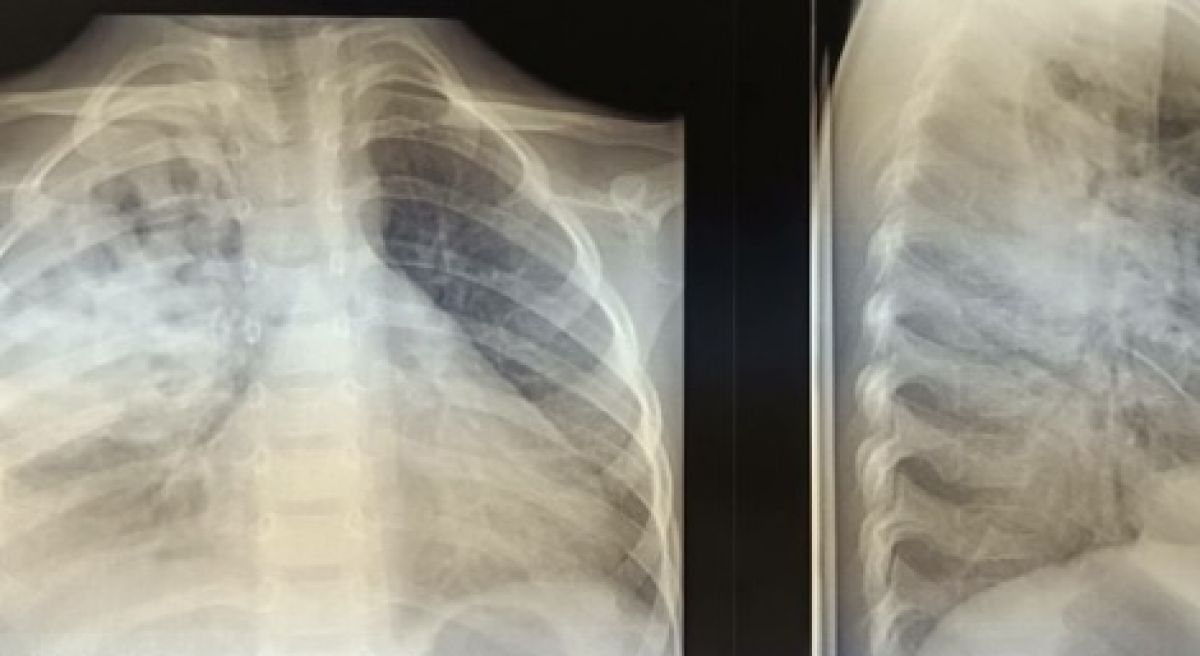

Владимирские врачи вылечили ребенка от тяжелой формы гнойной пневмонии Врачи-педиатры смогли поставить на ноги ребенка с тяжелой формы пневмонии со скоплением гноя и воздуха в плевральной полости,

Врачи-педиатры смогли поставить на ноги ребенка с тяжелой формы пневмонии со скоплением гноя и воздуха в плевральной полости, рассказали в областной детской клинической больнице.

По словам медиков, потребовалось проведение  дренирования плевральной полости. Затем юному пациенту назначили физиотерапию и подобрали терапию. В настоящее время малыш уже выписан домой.